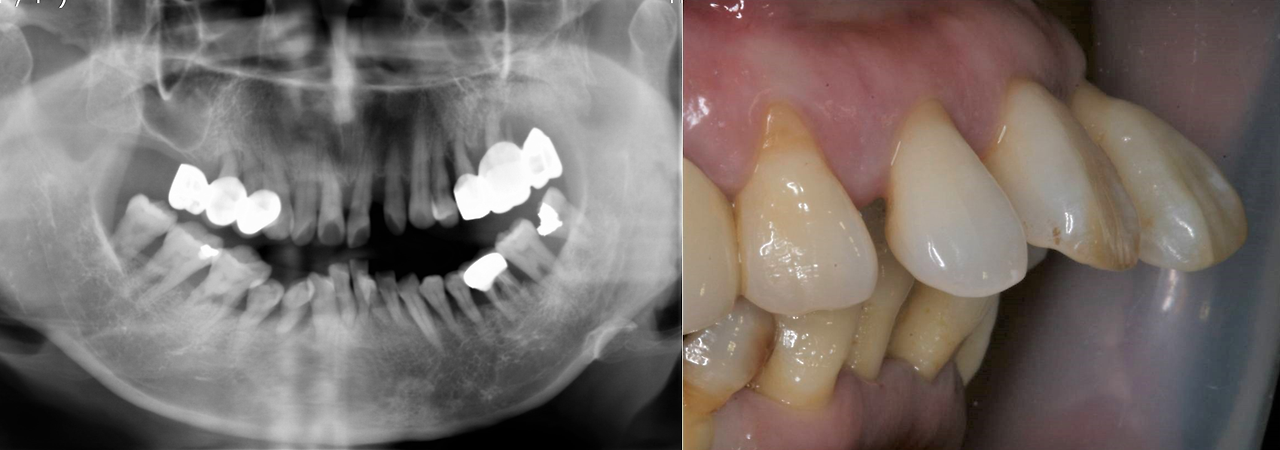

실제로 다음과 같은 치아 상태로 내원하신 분이 있었습니다.

치아를 잡고 있는 뼈가 많이 녹아서 흔들리는 치아가 많고 앞니는 흔들리면서 앞으로 많이 돌출된 뻐드렁니가 되었습니다. 식사하기 많이 불편한데도 다른 치과에서는 쓰는 데까지 쓰다가 정 불편할 때 이를 다 뽑고 완전틀니를 하든지 임플란트를 하자고 했다더군요. 치과마다 치료계획은 틀리겠지만 이 경우 저는 치주 보철을 이용합니다.

동요도가 너무 심해서 도저히 사용할 수 없는 상악의 구치부 보철물과 하악의 전치부와 소구치를 제외한 나머지 치아는 치주 보철로 계획하고 자연치로 연결할 수 없는 상악의 구치부는 최소한의 임플란트로 뽑은 자리를 대체하기로 했습니다. 위 증례를 치주 보철과 최소의 임플란트로 대체한 치료는 아래와 같습니다. 현재 10여 년 가까이 별문제 없이 사용하고 계십니다.